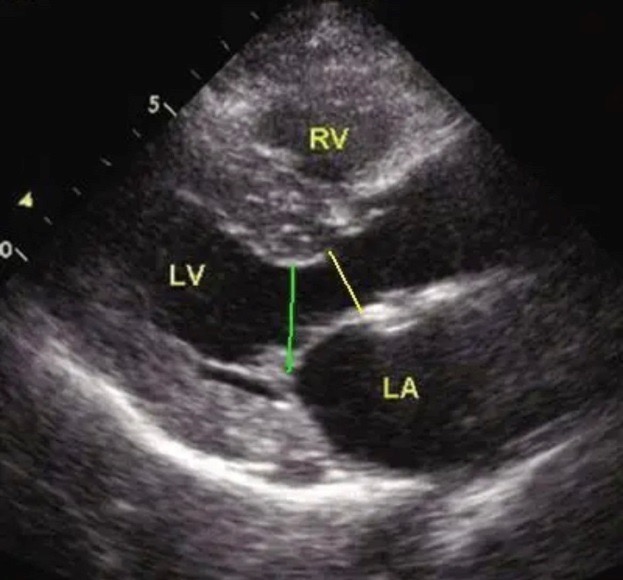

超声心动图:胸骨旁左室长轴切面可见左室壁明显肥厚,以室间隔和左室前壁肥厚为著。乳头肌水平室间隔最厚处约23.3mm,位于主动脉瓣下21mm处,前壁室壁厚21.5mm,侧壁室壁厚18.1mm,后壁室壁厚17.5mm。肥厚心肌运动僵硬。

超声心动图